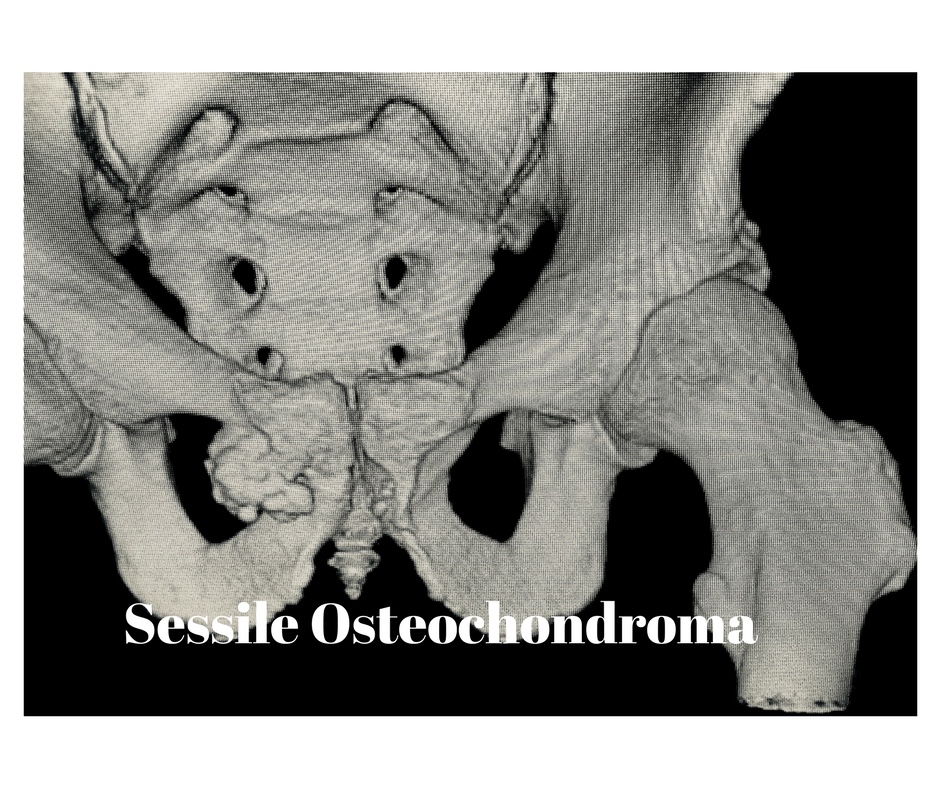

Now through this which was a bit of a scare and getting yelled out by the specialist and my daughter i’m going for a Nuclear Bone Scan full body as i have problems with walking on the right side they seem to feel that the Sessile Osteochondroma in my pelvic area has grown and hitting a nerve which is causing problems and server pain every now and then, so there doing a full body scan to see if i have any other problems occurring through this ageing old body. Now i’m going for the big three as i’m booked in for the Prostrate Cancer examination as well, i looked at it it’s time to look at my life of health a bit more seriously as when we are in our sixties we need to get these regular check ups to live a good a healthy life through the later years of life.